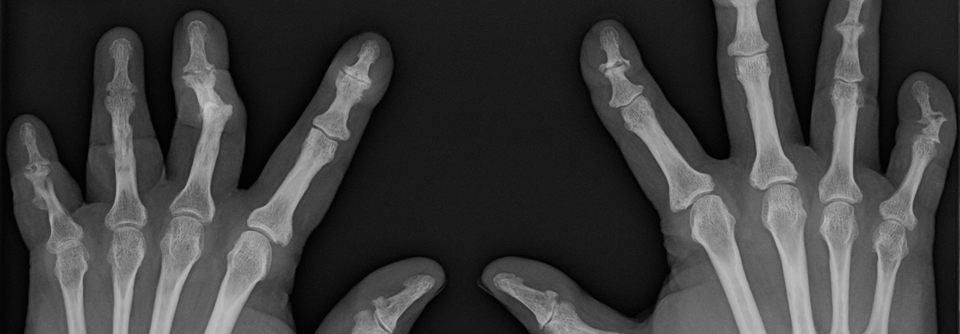

Sind beispielsweise ausschließlich Fingerendgelenke betroffen, spricht dies für eine Psoriasisarthritis. Gleiches gilt für die Daktylitis, also den Befall der Gelenke eines Fingers im Strahl inklusive Weichteilschwellung zum „Wurstfinger“. Die Arthropathie bei Hämochromatose wiederum macht sich insbesondere an den Grundgelenken von Finger 2 bis 5 sowie am proximalen Handgelenk breit. Besonders wichtig ist die Unterscheidung zwischen Arthritis und Arthrose: Letztere entwickelt sich insbesondere an den Fingerend- und -mittelgelenken sowie an allen Gelenken des Daumens. Die rheumatoide Arthritis befällt dagegen so gut wie nie die Fingerendgelenke, dafür jedoch ihre Mittel- und Grundgelenke und am Daumen bevorzugt das Grundgelenk.

Schlussendlich ist in vielen Fällen das traditionelle Röntgenbild ein guter Berater. Polyarthrose, rheumatoide Arthritis und Chondrokalzinose lassen sich durch Lokalisation und Art des Befalls meist gut identifizieren.